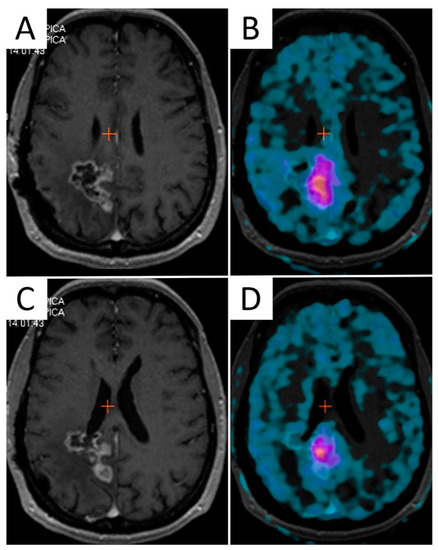

Figure 3.

The mismatch between contrast-enhanced T1-weighted MRI and 3,4-dihydroxy-6-[18F]fluoro-L-phenylalanine (F-DOPA) PET/CT in a 45-year-old female patient with recurrent GBM after multimodal first-line therapy. Two axial contrast-enhanced T1-weighted images (A,C) along with corresponding F-DOPA PET/CT slices (B,D) identifying different volumes of disease.